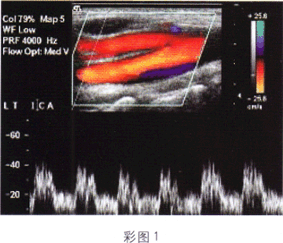

3.如圖所示(彩圖1),該頻譜波形符合下列哪支血管的頻譜特點

A.頸外動脈

B.頸內動脈

C.頸總動脈遠心段

D.頸內靜脈

E.椎動脈起始段

正確答案:B解題思路:頸內動脈頻譜為低速低阻。